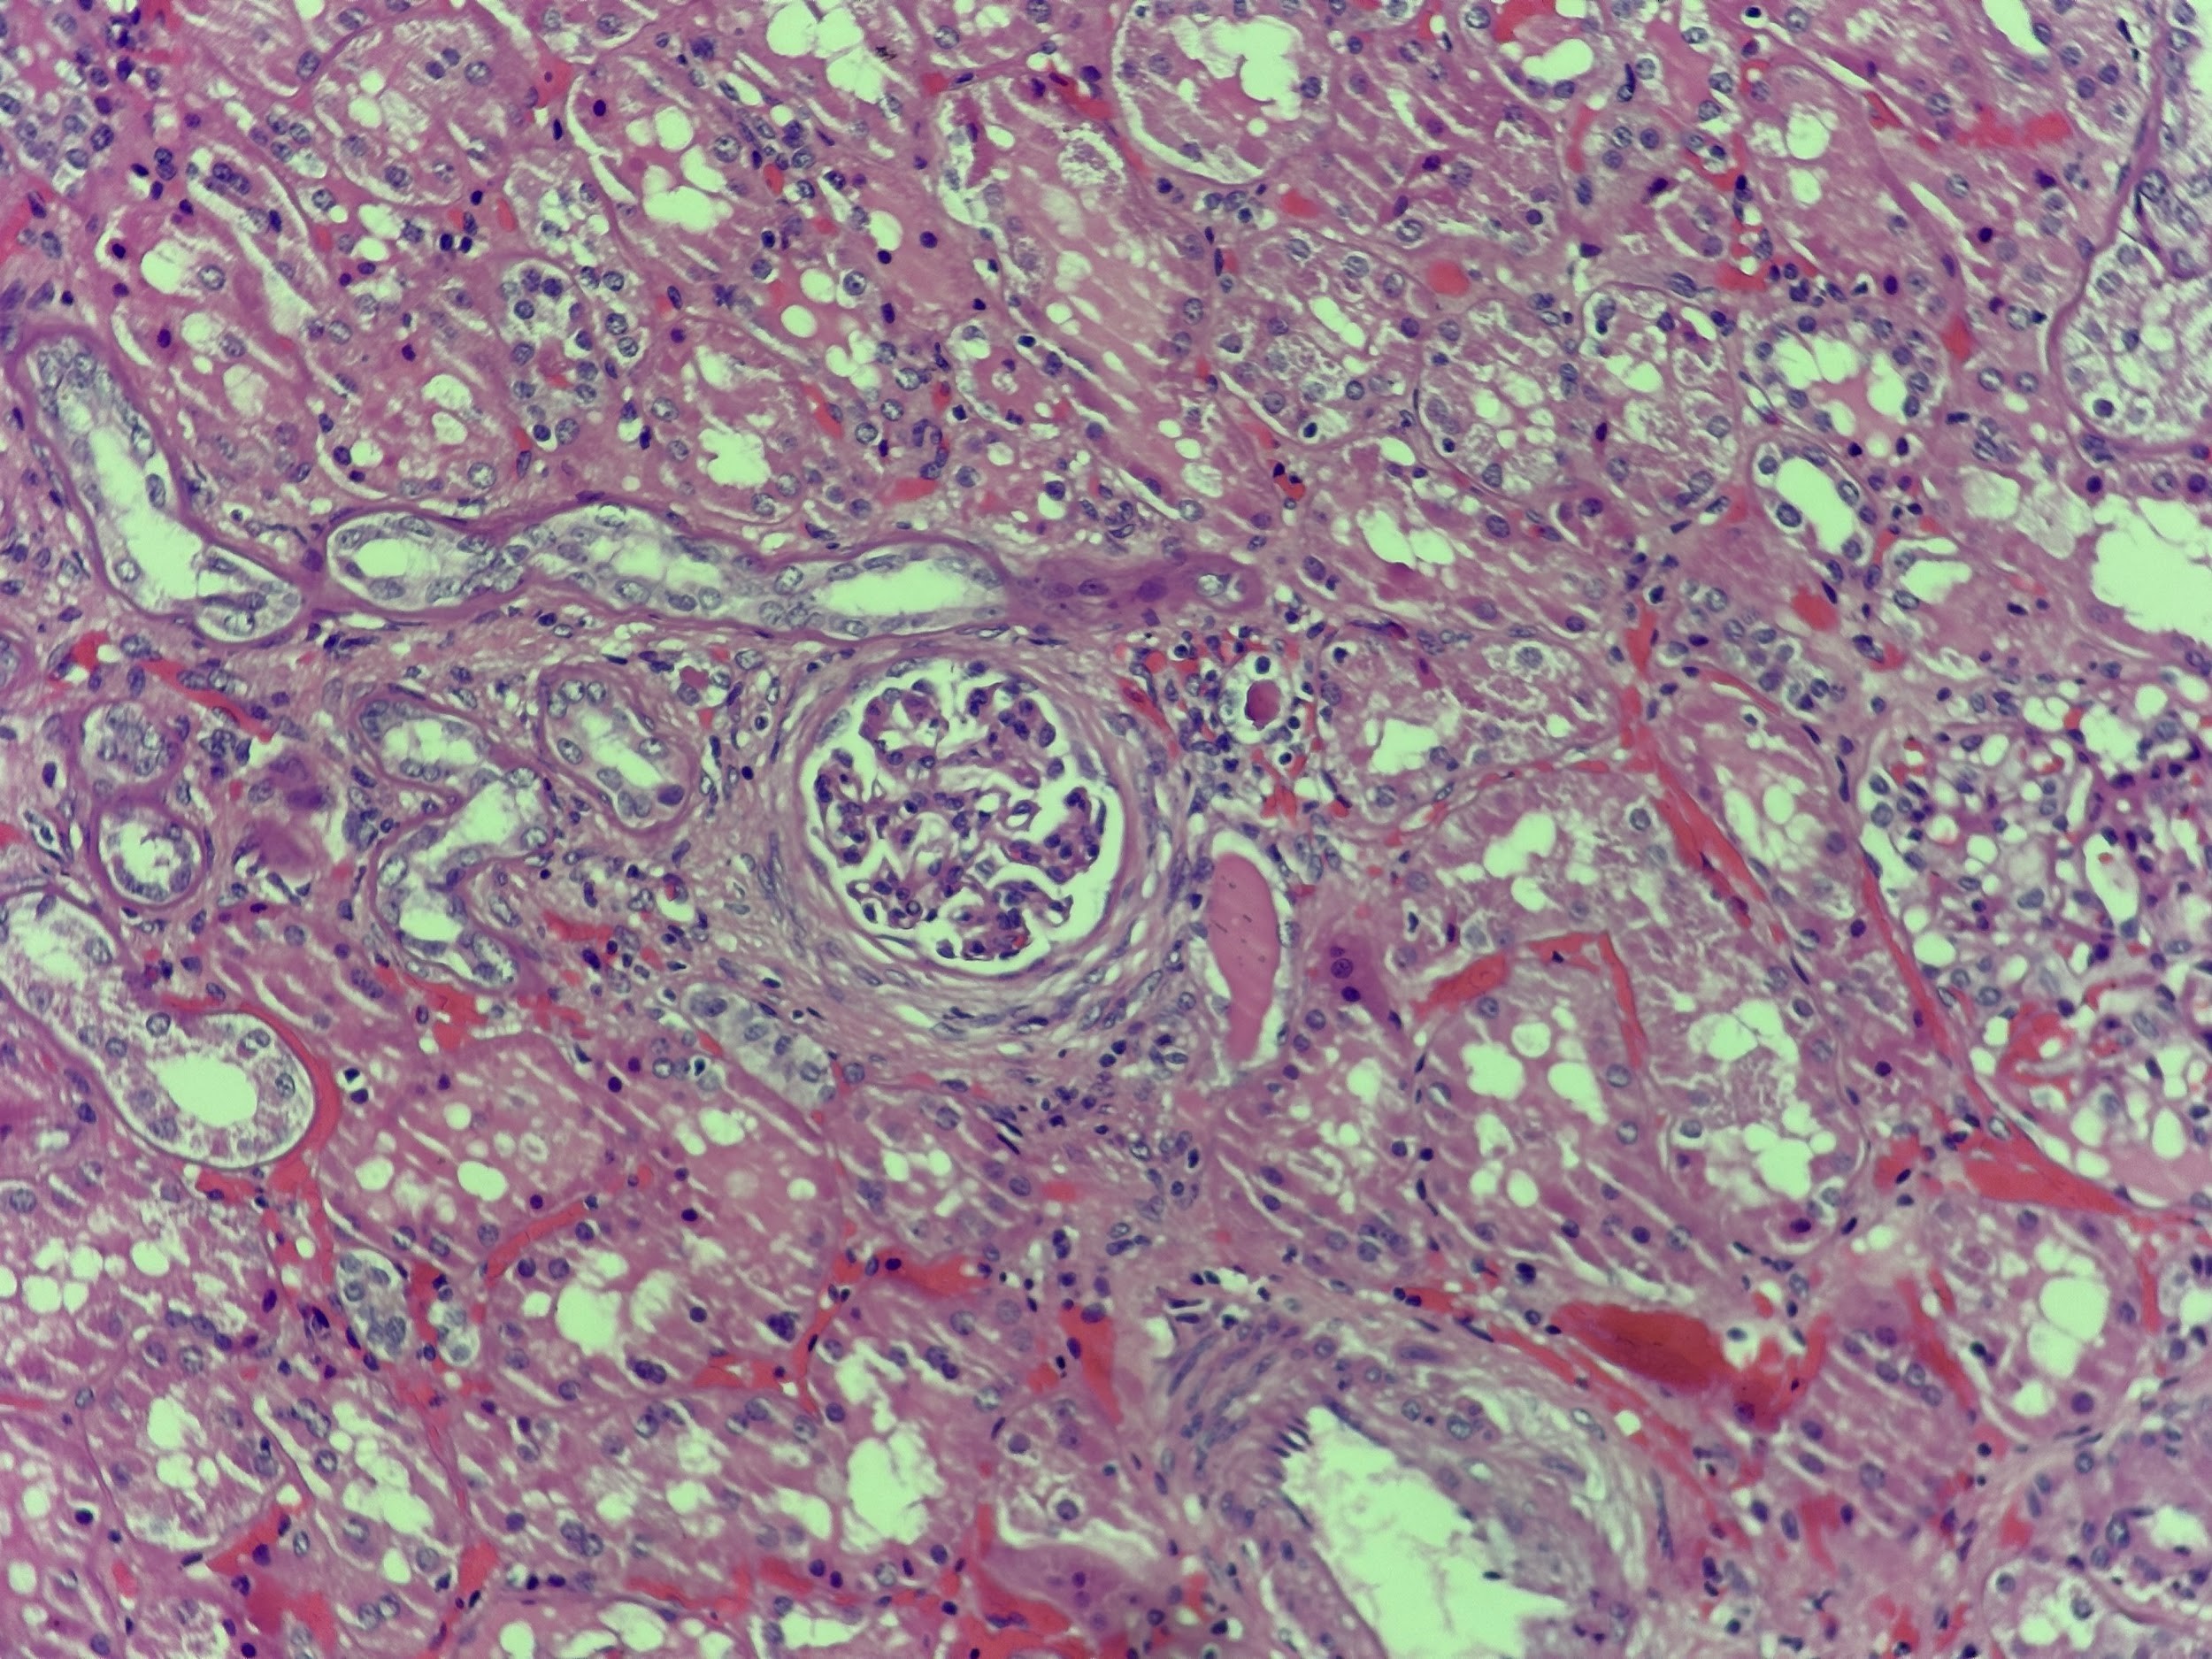

ESTUDIO HISTOPATOLÓGICO

En el centro de la microscopía, se aprecia un glomérulo, que indica estar parcialmente esclerosado y con retraimiento del penacho glomerular. Hay aumento de la matriz mesangial y engrosamiento focal de las asas capilares, aunque no hay proliferación evidente ni signos de inflamación activa en este campo. Destaca, además, la pérdida de la arquitectura tubular normal en varias zonas, y atrofia tubular severa con epitelio aplanado. Se observa fibrosis intersticial difusa, lo que indica un proceso crónico (figura 8).

Imagen 8:Corte histológico del riñón teñido con hematoxilina y eosina (40x). El patrón evidencia atrofia tubular severa, fibrosis intersticial extensa, nefritis intersticial, esclerosis glomerular parcial y cambios vasculares necróticos, hallazgos compatibles con nefropatía obstructiva crónica. Fuente: Dr. Alvarado, departamento de patología del Hospital Regional Dr. Rafael Hernández.